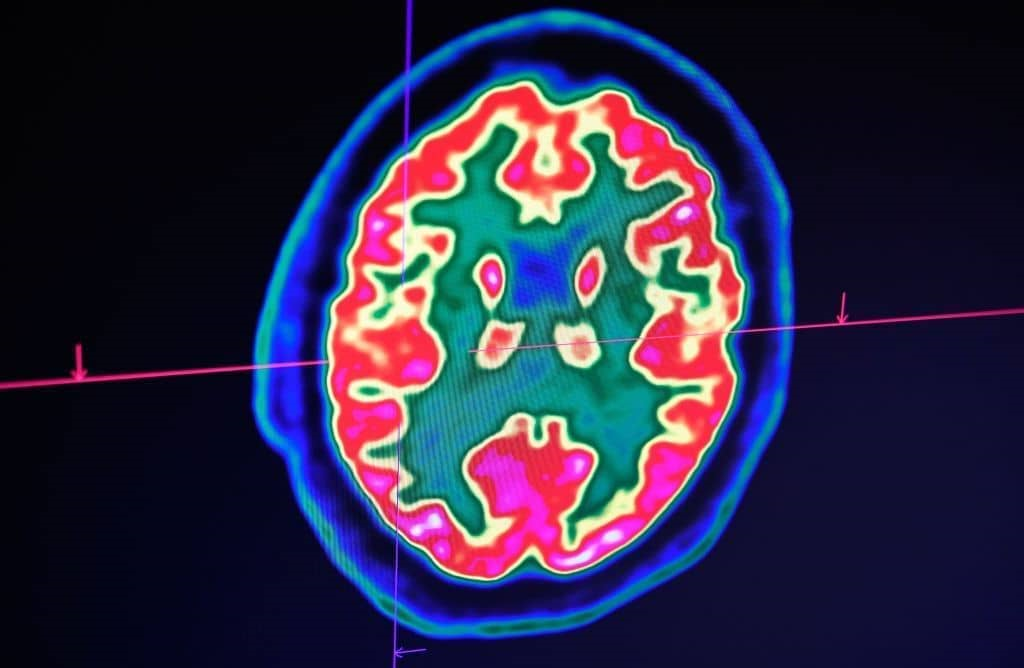

在过去的几年里,我们看到了一些显著的神经科学突破。在一项研究中,科学家们设法与瘫痪的病人进行交流,只要求他想象自己的想法,写下自己的想法。当他这样做时,大脑植入物记录了他运动皮层中的电信号,随后人工智能以94%的准确率解码了这些信号。在另一项研究中,科学家追踪了 "思想在大脑中的进展":参与者被要求思考一个特定单词的反义词,植入大脑皮层的电极显示了这个过程的每一步--刺激感知、单词选择和反应--是如何被 "传递 "到大脑的不同部分。在一项具有里程碑意义的研究中,科学家们声称终于找到了大脑中与“觉醒”和“意识”有关的三个特定区域,它们与意识的形成有关。

以目前最流行的科学"意识理论 ":综合信息理论(IIT)为例。IIT从一个有趣的观察开始:意识似乎与特定大脑区域的神经元数量没有什么关系。例如,小脑占了大脑860亿个神经元中的690亿个,但它在意识体验中根本没有发挥任何重要作用,而小得多的大脑却发挥了作用。那么是什么造成了这种差异呢?根据IIT背后的策划者朱利奥-托诺尼(Giulio Tononi)的说法,是大脑中的神经元的相互联系要紧密得多。由此,托诺尼得出结论,产生意识的因素是一个系统中的"综合信息"量--他认为这可以用数学的精确度来计算,并用希腊字母Φ(Phi)来表示。